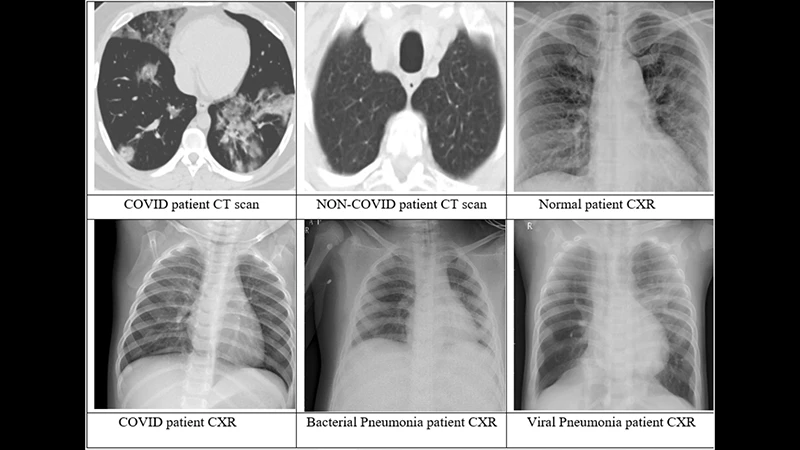

Both X-rays and CT (Computed Tomography) scans are common medical imaging tests that use X-ray radiation to see inside the body. While they are based on the same fundamental technology, they produce very different types of images and are used for different reasons. Think of a standard X-ray as a simple photograph and a CT scan as a highly detailed, 3D model.

- CT Scan: A CT scanner is a much more complex, doughnut-shaped machine. An X-ray source and detector spin rapidly around the patient, taking hundreds of X-ray "slices" from every angle. A powerful computer then reconstructs these slices into detailed, cross-sectional 2D images and can even assemble them into a 3D model.

- X-ray Image: An X-ray shows a 2D view where all the internal structures are superimposed on top of each other. For example, on a chest X-ray, the ribs, lungs, heart, and spine are all layered together. This can make it difficult to see small details behind other organs.

- CT Image: A CT scan eliminates this overlap. It provides a clear, cross-sectional view of one "slice" of the body at a time, as if you were looking at a single slice of a loaf of bread. This allows doctors to see the precise size, shape, and location of organs and abnormalities with incredible clarity.